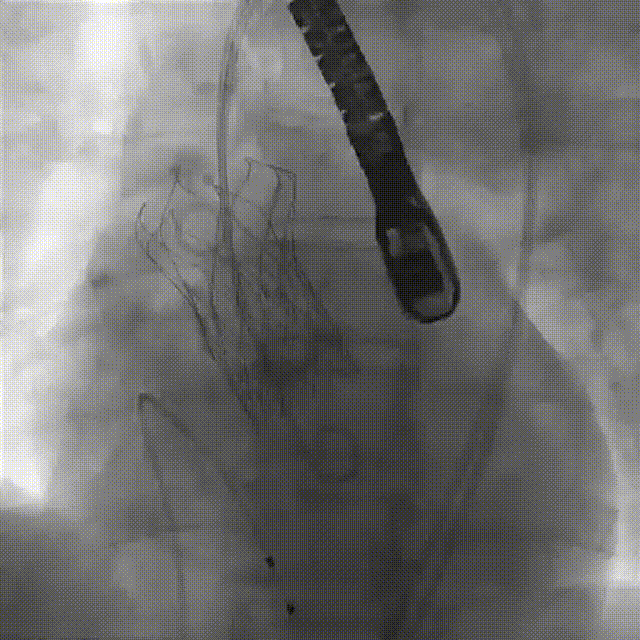

24mm球囊预扩

患者全麻,气管插管。经左侧股动脉作为辅入路,将6F猪尾巴导管送至无冠窦窦底,右股动脉作为主入路,右侧股动脉作为主入路,置入18F大鞘,先行主动脉根部造影,可见术前有轻中度返流,行24mm球囊进行预扩,无瓣周漏,无明显腰征,双侧冠脉血流通畅,决定按计划选择27# VitaFlow Liberty™瓣膜,在王建安教授的线上指导、刘先宝教授的现场支持下,将瓣膜释放至功能位,再次造影发现瓣膜位置偏高,遂进行回收,再次释放,最终脱钩,再次造影确认瓣膜位置及形态良好,压差从术前的80mmHg降低至2mmHg,无瓣周漏。